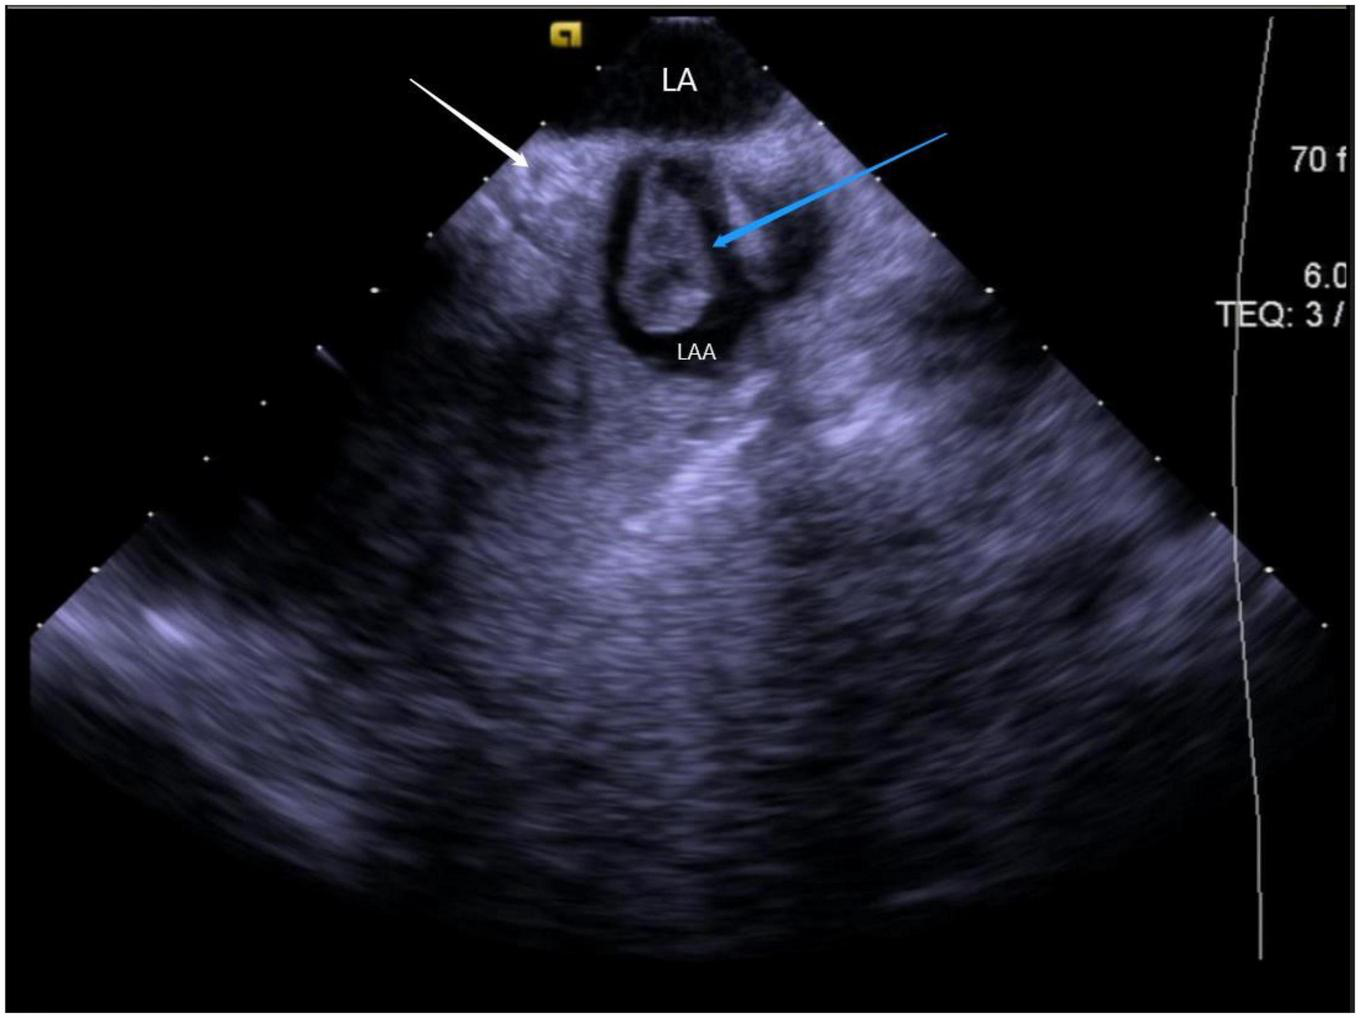

The left ventricular summit (LVS) is the triangular region at the most superior part of the LV epicardial surface consisting of the left circumflex coronary artery, the left anterior descending artery, and an approximate line from the first septal coronary artery laterally to the left AV groove. As the LVS region is bisected by the great cardiac vein (GCV), an area superior to it is inaccessible to catheter ablation due to the proximity of the coronary arteries and overlying epicardial fat (26). It is suggested that PVCs in this area sometimes require “anatomical ablation,” and the successful target may not be the earliest source of excitement (27). In the traditional 3D model, the presence of an unexplored area might result in incomplete model construction and ablation failure. Hence, coronary angiography or cardiac venography is usually used to guide the localization, while the distance between the ablation catheter and the epicardial coronary artery exceeding 0.5 cm is considered safe to avoid vascular damage (28). However, some studies have revealed that catheter ablation of adjacent structures like the aortic valve and RVOT under ICE-assisted imaging is highly effective (29) (Figure 6). Furthermore, although the selective resolution of the ICE prohibits the viewing of the small veins, the operator can successfully perform ablation in the branch without venography. Rivera et al. reported successful zero-ray ablation procedures in 26 cases of PVC/VT originating from the LVS region, with an immediate success rate of 84% due to the guidance of an ICE-guided 3D electroanatomical mapping system without any serious complications (30).

FIGURE 6

ICE view of the aortic root and pulmonary artery at the left ventricular summit region, viewed from the right ventricular outflow tract. At the center, a short axe of the left main coronary artery (LMCA) (blue arrow) surrounded by a thick layer of adipose tissue (LVS). RCC, right coronary cusp; LCC, left coronary cusp; LA, left atrial; LAA, left atrial appendage; PA, pulmonary artery; The LVS is marked with an X.